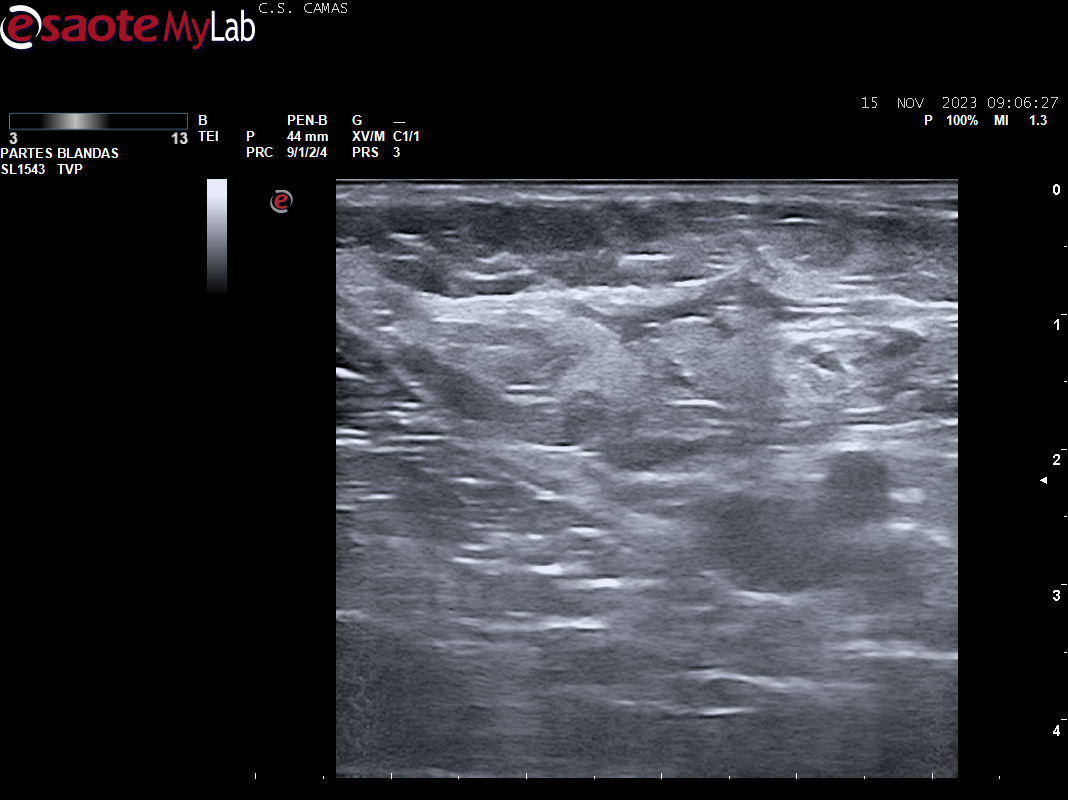

A la exploración se aprecia cordón varicoso en cara interna del muslo izq. Se realiza POCUS en consulta para descartar la presencia de TVP.

Ecografia vascular cara interna del muslo izq: Trombosis de todo el recorrido de la safena izq con dolor al paso de la sonda por colaterales inferiores que colapsan. Presenta además en zona del cayado de la safena imagen heterogenea sin apreciar la llegada de la safena a la femoral común compatible con arrancamiento de la misma.

Trombosis de todo el recorrido de la safena interna izquierda con tromboflebitis de las colaterales inferiores que concuerda con el diagnóstico hospitalario.